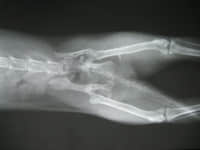

这次跳楼的代价就是骨盆整个碎裂,主人很心疼,找了我们附近的一家著名的动物医院拍摄了x光片,咨询了学校动物医院,又咨询了天河某家动物诊所,最后转介到我们医院进行手术治疗。我很痛心,因为再没有人接下这个病例的话,这只猫咪不能排便,很容易就挂掉了。像这种深部手术,需要分离的肌肉软组织非常多,碎裂的部位刚好在坐骨大神经下面,手术比较难,我很郁闷很郁闷。转介到上海或者北京的宠物医院也不太现实。只能硬这头皮接下来做了。并且告诉主人最可能的结果是什么。

我们也数不清楚到底骨盆碎了多少块,只知道手术拿出来的碎骨就有十几块。部分碎骨掉到盆抢深处,插到直肠里面去。右侧股骨头掉到盆腔,压迫直肠。整个髋关节全部碎